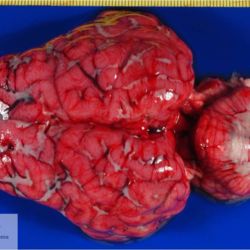

Pàgina anterior de 637 Pàgina següent 3181 total Ovine Specie: Ovine Organ: Brain Lesion: Meningitis Lesion modifier: Meningitis - Fibrinous-purulent Disease: - Not viewed Ovine Specie: Ovine Organ: Lung Lesion: Atelectasis Lesion modifier: - Disease: - Files/Expedient: Leon15 Position: 136 (2 views) Ovine Specie: Ovine Organ: Lung Lesion: Atelectasis Lesion modifier: - Disease: - Files/Expedient: Leon15 Position: 87 (3 views) Ovine Specie: Ovine Organ: Lung Lesion: Bronchitis Lesion modifier: - Disease: Dictyocaulosis Files/Expedient: Leon12 Position: 253 (1 views) Bovine Specie: Bovine Organ: Lung Lesion: Bronchopneumonia Lesion modifier: Bronchopneumonia - Catarrhal-purulent Disease: - Position: 253 (1 views) Pàgina anterior de 637 Pàgina següent Títol Select...Avian (Exotic) (110)Avian (Poultry) (76)Bovine (317)Canine (935)Caprine (47)Equine (257)Feline (326)Ferret (19)General (127)Marine mammal (22)Non-human primate (20)Ovine (328)Porcine (379)Rabbit (61)Reptile (38)Rodent (28)Wildlife (91) Format Select...- (60)Abomasum (37)Adrenal gland (10)Blood (7)Blood vessel (50)Body as a whole (19)Bone (57)Bone marrow (21)Brain (93)Cloaca (1)Diaphragm (2)Ear (5)Esophagus (39)Eye (16)Fetus (12)Gallbladder (23)Gizzard (2)Heart (265)Intestine (356)Joint (32)Kidney (443)Larynx (5)Liver (326)Lung (264)Lymph node (91)Mammary gland (10)Mediastinum (1)Muscle (22)Nasal cavity (22)Nerve (7)Omasum (5)Oral cavity (63)Ovary (14)Oviduct (8)Pancreas (7)Parathyroid (5)Penis (10)Peritoneum (65)Pharynx (9)Pituitary gland (6)Placenta (7)Prostate (8)Proventriculus (3)Reticulum (1)Rumen (28)Sinus (7)Skin (181)Spinal cord (15)Spleen (105)Stomach (125)Teeth (1)Testicle (11)Thoracic cavity (31)Thymus (13)Thyroid gland (5)Tongue (32)Tonsils (11)Trachea (11)Urethra (5)Urinay bladder (61)Uterus (27)Vagina (1)Vulva (1)Yolk sac (1) Cobertura Select...- (152)Abomasitis (26)Abscess (27)Acidosis (1)Adenocarcinoma (20)Adenoma (9)Aerosacculitis (6)Agenesis (1)Agnathia (1)Alopecia (7)Amyloidosis (12)Aneurysm (6)Angiectasis (1)Anthracosis (1)Arteritis (11)Arthritis (15)Arthrogryposis (6)Artifact (4)Ascites (13)Atelectasis (8)Atherosclerosis (5)Atresia (1)Atrial septal defect (2)Atrophy (10)Autolysis (7)Bronchitis (6)Bronchopneumonia (26)Cachexia (2)Carcinoma (103)Cardiomyopathy (19)Cellulitis (2)Chemodectoma (4)Cholangiohepatitis (4)Cholangitis (19)Cholecystitis (4)Cholestasis (5)Chondrodysplasia (2)Chondrosarcoma (2)Chronic passive congestion (13)Chylothorax (2)Cirrhosis (6)Coelomitis (3)Coenurus cerebralis (4)Colitis (40)Congestion (17)Conjunctivitis (5)Coronitis (3)Cryptorchidism (3)Cyst (25)Cystitis (24)Dermatitis (69)Diaphragmatic hernia (4)Dilation (28)Discospondylitis (1)Disseminated intravascular coagulation (7)Dyschondroplasia (1)Dysplasia (29)Ectopia cordis (1)Ectopic ureter (1)Edema (55)Emphysema (5)Encephalitis (5)Endocardiosis (14)Endocarditis (26)Endometritis (5)Enteritis (118)Enterolith (6)Epulis (3)Esophagitis (14)Fasciitis (1)Fibrosis (7)Fibrous osteodystrophy (8)Fistula (1)Folliculitis (3)Fracture (2)Gastritis (34)Gingivitis (5)Glioma (8)Glomerulonephritis (21)Glossitis (25)Glycogenosis (1)Gout (8)Granuloma (2)Granulosa cell tumor (4)Hemangioma (9)Hemangiosarcoma (46)Hematoma (8)Hemoglobinuria (2)Hemopericardium (12)Hemoperitoneum (2)Hemorrhage (100)Hemosiderosis (7)Hemothorax (2)Hepatitis (78)Hernia (11)Histiocytosis (3)Hydatid cyst (11)Hydrocephalus (9)Hydrometra (1)Hydronephrosis (22)Hydropericardium (6)Hydrothorax (3)Hydroureter (5)Hyperkeratosis (8)Hyperostosis (4)Hyperplasia (37)Hypertrophy (9)Hypopigmentation (1)Hypoplasia (7)Hypopyon (1)Impaction (6)Infarction (63)Insulinoma (6)Intussusception (5)Jaundice (17)Laminitis (2)Laryngitis (2)Leiomyoma (5)Leukemia (13)Lipidosis (36)Lipoma (7)Lymphadenitis (45)Lymphadenopathy (7)Lymphangiectasia (6)Lymphangitis (5)Lymphoma (221)Malacia (11)Malignant melanoma (15)Mast cell tumor (11)Mastitis (8)Megaesophagus (2)Melanosis (3)Melena (4)Meningioma (6)Meningitis (6)Meningocele (2)Meningoencephalitis (5)Mesothelioma (5)Methemoglobinemia (2)Mineralization (10)Mucocele (5)Mucometra (1)Multilobular bone tumor (1)Mummification (3)Myelofibrosis (1)Myocarditis (4)Myositis (5)Necrosis (81)Nephritis (113)Nephroblastoma (6)Nephrosclerosis (1)Nephrosis (14)Neuritis (1)Obstruction (13)Omasitis (4)Omphalitis (1)Omphalophlebitis (7)Orchitis (4)Osteoarthrosis (5)Osteomyelitis (9)Otitis (2)Palatoschisis (3)Pancreatitis (3)Panniculitis (3)Papilloma (7)Parakeratosis (14)Patent ductus arteriosus (6)Peliosis hepatis (1)Perforation (17)Pericarditis (35)Peritonitis (39)Persistent right aortic arch (1)Pharyngitis (2)Pheochromocytoma (2)Phlebitis (2)Placentitis (6)Pleuritis (21)Pleuropneumonia (24)Pneumonia (109)Pneumothorax (3)Polycystosis (14)Polyp (5)Polyserositis (6)Posthitis (1)Proctitis (4)Prolapse (3)Prostatitis (3)Proventriculitis (1)Pyelonephritis (24)Pyometra (6)Pyothorax (4)Rhinitis (11)Rumenitis (6)Rupture (24)Salpingitis (3)Sarcoma (57)Sclerosis (1)Scoliosis (2)Seminoma (2)Sequestrum (2)Serous atrophy (14)Sinusitis (7)Splenitis (14)Splenomegaly (9)Spondylitis (6)Spondylosis (1)Stenosis (9)Stomatitis (32)Tenosynovitis (2)Teratoma (3)Thricobezoar (2)Thrombosis (16)Tonsilitis (4)Torsion (13)Tracheitis (4)Tympany (7)Typhlitis (8)Typhlocolitis (4)Ulcer (43)Urethritis (1)Urolithiasis (36)Uroperitoneum (1)Uveitis (1)Vasculitis (15)Ventricular septal defect (3)Volvulus (11) Matèria Select... - (14)- (1653)- (152)Abomasitis - Catarrhal (2)Abomasitis - Catarrhal-hemorrhagic (1)Abomasitis - Chronic (1)Abomasitis - Fibrinous-necrotizing (2)Abomasitis - Hyperplasic (5)Abomasitis - Hyperplasic - Chronic (1)Abomasitis - Necrotic (1)Abomasitis - Necrotizing (2)Abomasitis - Ulcerative (5)Adenocarcinoma (9)Aerosacculitis - Granulomatous (1)Amyloidosis - Chronic (1)Arteritis - Necrotic (2)Arteritis - Necrotizing (1)Arthritis - Chronic (4)Arthritis - Fibrinous-purulent (3)Arthritis - Serous (4)Arthritis - Subacute (1)Ascites - Serous (1)Atrophy - Serous (1)Bronchitis - Catarrhal (3)Bronchitis - Suppurative (1)Bronchopneumonia - Catarrhal-purulent (17)Bronchopneumonia - Fibrinous (1)Bronchopneumonia - Granulomatous (1)Bronchopneumonia - Purulent (1)Bronchopneumonia - Suppurative (5)Carcinoma - Adenocarcinoma (33)Carcinoma - Adenocarcinoma - Hepatocellular (2)Carcinoma - Adenocarcinoma - Mucinous (1)Carcinoma - Basosquamous (1)Carcinoma - Cholangiocellular (3)Carcinoma - Hepatocellular (4)Carcinoma - Metastatic (3)Carcinoma - Squamous cell carcinoma (13)Carcinoma - Transitional cell (2)Cardiomyopathy - Dilated (13)Cardiomyopathy - Hypertrophic (6)Cellulitis - Necrotizing (1)Cholangitis - Chronic (8)Cholangitis - Hyperplasic (3)Cholecystitis - Fibrinous-necrotizing (1)Coelomitis - Fibrinous (1)Coelomitis - Granulomatous (1)Colitis - Catarrhal (3)Colitis - Catarrhal-hemorrhagic (1)Colitis - Fibrinous (1)Colitis - Fibrinous-necrotizing (1)Colitis - Fibrinous-necrotizing (Diphtheritic) (6)Colitis - Granulomatous (2)Colitis - Hemorrhagic (4)Colitis - Hemorrhagic-necrotizing (3)Colitis - Necrotizing (2)Colitis - Ulcerative (6)Congestion - Chronic (2)Conjunctivitis - Hyperplasic (1)Conjunctivitis - Purulent (3)Coronitis - Ulcerative (1)Cystitis - Chronic (3)Cystitis - Fibrinous (1)Cystitis - Fibrinous-necrotizing (1)Cystitis - Follicular (1)Cystitis - Hemorrhagic (6)Cystitis - Hemorrhagic-ulcerative (1)Cystitis - Necrotizing (9)Cystitis - Perforated (1)Dermatitis - Granulomatous (14)Dermatitis - Hyperkeratotic (10)Dermatitis - Hyperplasic (proliferative) (1)Dermatitis - Hyperplastic (10)Dermatitis - Necrotizing (4)Dermatitis - Pustular (4)Dermatitis - Ulcerative (2)Dilation - Chronic (1)Discospondylitis - Necrotizing (1)Dysplasia - Follicular (5)Edema - Interstitial (6)Emphysema - Interstitial (1)Encephalitis - Granulomatous (1)Encephalitis - Nonsuppurative (1)Endocardiosis - Mitral (7)Endocardiosis - Mitral - Chronic (5)Endocarditis - Valvular (6)Endocarditis - Valvular - Mitral (7)Endocarditis - Valvular - Pulmonic (1)Endocarditis - Valvular - Subacute (1)Endocarditis - Valvular - Subaortic (5)Endocarditis - Valvular - Tricuspid (4)Endometritis - Purulent (3)Endometritis - Purulent-hemorrhagic (2)Enteritis - Catarrhal (23)Enteritis - Catarrhal - Acute (1)Enteritis - Catarrhal-hemorrhagic (5)Enteritis - Catarrhal-hemorrhagic - Acute (2)Enteritis - Fibrinous (16)Enteritis - Fibrinous - Acute (3)Enteritis - Fibrinous-necrotizing (7)Enteritis - Granulomatous (14)Enteritis - Granulomatous - Chronic (1)Enteritis - Granulomatous - Multifocal (1)Enteritis - Hemorrhagic (17)Enteritis - Hemorrhagic - Acute (1)Enteritis - Hemorrhagic-necrotizing (1)Enteritis - Hyperplasic (proliferative) (4)Enteritis - Necrotizing (4)Enteritis - Necrotizing - Acute (1)Enteritis - Necrotizing - Hemorrhagic (1)Enteritis - Necrotizing-ulcerative (2)Enteritis - Ulcerative (1)Enteritis - Ulcerative-hemorrhagic (1)Esophagitis - Erosive-ulcerative (6)Esophagitis - Necrotizing (4)Esophagitis - Ulcerative (1)Esophagitis - Ulcerative-necrotizing (1)Fasciitis - Fibrinous-purulent (1)Folliculitis - Purulent (2)Gastritis - Catarrhal (2)Gastritis - Chronic (1)Gastritis - Follicular (1)Gastritis - Hemorrhagic (2)Gastritis - Hemorrhagic-necrotizing (1)Gastritis - Hypertrophic (2)Gastritis - Inclusion bodies (1)Gastritis - Mineralization (1)Gastritis - Mycotic (1)Gastritis - Necrotizing (2)Gastritis - Ulcerative (6)Gastritis - Uremic (3)Gingivitis - Erosive (2)Gingivitis - Hyperplasic (proliferative) (1)Gingivitis - Necrotizing (1)Glomerulonephritis - Chronic (7)Glomerulonephritis - Membranoproliferative (3)Glomerulonephritis - Membranoproliferative - Chronic (1)Glomerulonephritis - Membranous (3)Glomerulonephritis - Membranous - Chronic (1)Glomerulonephritis - Proliferative (2)Glomerulonephritis - Subacute (1)Glossitis - Erosive (2)Glossitis - Granulomatous (6)Glossitis - Hyperplasic (1)Glossitis - Hyperplasic (proliferative) (2)Glossitis - Hyperplastic (1)Glossitis - Necrotizing (2)Glossitis - Necrotizing - Focal (1)Glossitis - Ulcerative (6)Glossitis - Ulcerative - Multifocal (1)Glossitis - Ulcerative - Subacute (1)Glycogenosis (1)Granuloma - Eosinophilic (1)Hemangiosarcoma - Metastatic (2)Hemorrhage - Acute (1)Hemorrhage - Subcapsular (3)Hepatitis - Abscess (9)Hepatitis - Acute (3)Hepatitis - Chronic (4)Hepatitis - Chronic interstitial (6)Hepatitis - Granulomatous (7)Hepatitis - Interstitial - Multifocal (1)Hepatitis - Interstitial - Subacute (1)Hepatitis - Necrotizing (17)Hepatitis - Necrotizing - Acute (2)Hepatitis - Necrotizing - Hemorrhagic (1)Hepatitis - Necrotizing - Subacute (1)Hepatitis - Pyogranulomatous (7)Hepatitis - Subacute (4)Hydronephrosis - Chronic (1)Hydropericardium - Chronic (1)Hyperplasia - Erythroid (1)Hyperplasia - Lymphoid (3)Hyperplasia - Myeloid (1)Hyperplasia - Nodular (8)Hypertrophy - Concentric (2)Hypertrophy - Eccentric (3)Infarction - Acute (17)Infarction - Acute - Multifocal (2)Infarction - Chronic (5)Infarction - Chronic - Multifocal (1)Infarction - Subacute (18)Infarction - Subacute - Focal (2)Laminitis - Chronic (2)Laryngitis - Necrotic (1)Laryngitis - Necrotizing (1)Leukemia - Lymphoid leukemia (2)Leukemia - Non-lymphoid leukemia (6)Lipidosis - Multifocal (1)Lipidosis - Panlobular (1)Lipidosis - Panlobular - Generalized (2)Lymphadenitis - Granulomatous (24)Lymphadenitis - Granulomatous - Chronic (3)Lymphadenitis - Hemorrhagic (1)Lymphadenitis - Necrotizing (5)Lymphadenitis - Necrotizing (caseous) (11)Lymphangitis - Granulomatous (1)Lymphangitis - Purulent (1)Lymphangitis - Ulcerative (1)Lymphoma - Alimentary lymphoma (7)Lymphoma - Cutaneous lymphoma (6)Lymphoma - Lymphosarcoma (2)Lymphoma - Mediastinal lymphoma (1)Lymphoma - Multicentric lymphoma (29)Malignant melanoma - Malignant (1)Malignant melanoma - Metastatic (1)Mast cell tumor - Metastatic (1)Mastitis - Fibrinous-purulent (2)Mastitis - Necrotic (1)Mastitis - Purulent (3)Mastitis - Suppurative (1)Meningitis - Fibrinous-purulent (2)Meningitis - Purulent (4)Meningoencephalitis - Necrotizing (3)Meningoencephalitis - Nonsuppurative (2)Mineralization - Metastatic (4)Myocarditis - Fibrous - Chronic (1)Myocarditis - Granulomatous (1)Myositis - Purulent (2)Necrosis - Acute (1)Necrosis - Cortical (5)Necrosis - Follicular (1)Necrosis - Papillary (8)Necrosis - Papillary - Acute (3)Necrosis - Subacute (3)Necrosis - Tubular (6)Nephritis - Embolic (2)Nephritis - Embolic suppurative (7)Nephritis - Granulomatous (27)Nephritis - Granulomatous - Chronic (1)Nephritis - Granulomatous - Multifocal (1)Nephritis - Interstitial (6)Nephritis - Interstitial - Acute (4)Nephritis - Interstitial - Chronic (41)Nephritis - Interstitial - Subacute (12)Nephritis - Purulent (7)Nephritis - Purulent - Acute (2)Nephritis - Purulent - Multifocal (3)Nephrosis - Cholemic (3)Nephrosis - Hemoglobinuric (10)Omasitis - Fibrinous-necrotizing (1)Omasitis - Hyperkeratotic (1)Omasitis - Necrotizing (2)Omphalophlebitis - Fibrinous-purulent (2)Omphalophlebitis - Purulent (3)Orchitis - Necrotizing (1)Osteomyelitis - Necrotizing (7)Osteomyelitis - Purulent (2)Otitis - Necrotizing (1)Otitis - Proliferative (1)Pancreatitis - Acute (1)Pancreatitis - Chronic (1)Pancreatitis - Granulomatous (1)Panniculitis - Fibrinous-purulent (1)Panniculitis - Necrotic (1)Panniculitis - Parasitic (1)Perforation - Acute (2)Pericarditis - Fibrinous (19)Pericarditis - Fibrinous - Subacute (1)Pericarditis - Fibrinous-necrotizing (1)Pericarditis - Fibrinous-purulent (3)Pericarditis - Fibrous (1)Pericarditis - Fibrous - Chronic (1)Pericarditis - Gangrenous (6)Pericarditis - Granulomatous (1)Pericarditis - Granulomatous - Chronic (2)Peritonitis - Acute (1)Peritonitis - Fibrinous (11)Peritonitis - Fibrinous - Subacute (1)Peritonitis - Fibrinous-purulent (5)Peritonitis - Fibrous (3)Peritonitis - Granulomatous (6)Peritonitis - Purulent (1)Peritonitis - Purulent-hemorrhagic (1)Peritonitis - Pyogranulomatous (3)Pharyngitis - Fibrinous-necrotizing (1)Pharyngitis - Ulcerative (1)Pheochromocytoma - Metastatic (1)Phlebitis - Purulent (1)Placentitis - Fibrinous-necrotizing (1)Placentitis - Necrotic (1)Placentitis - Necrotizing (1)Pleuritis - Chronic (1)Pleuritis - Fibrinous (3)Pleuritis - Fibrinous-purulent (2)Pleuritis - Fibrous (2)Pleuritis - Granulomatous (3)Pleuritis - Hyperplastic (2)Pleuritis - Purulent (2)Pleuritis - Pyogranulomatous (1)Pleuropneumonia - Fibrinous (13)Pleuropneumonia - Fibrinous-necrotizing (5)Pleuropneumonia - Granulomatous (2)Pleuropneumonia - Hemorrhagic-necrotizing (4)Pneumonia - Aspiration (11)Pneumonia - Bronchointerstitial (4)Pneumonia - Bronchointerstitial - Subacute (1)Pneumonia - Embolic (5)Pneumonia - Granulomatous (37)Pneumonia - Granulomatous - Multifocal (4)Pneumonia - Hemorrhagic-necrotizing (2)Pneumonia - Interstitial (7)Pneumonia - Interstitial - Acute (8)Pneumonia - Interstitial - Chronic (6)Pneumonia - Interstitial - Subacute (15)Pneumonia - Necrotizing (2)Pneumonia - Pyogranulomatous (2)Pneumonia - Verminous (5)Polyserositis - Fibrinous (6)Polyserositis - Fibrous (1)Proctitis - Fibrinous-necrotizing (1)Proctitis - Parasitic (2)Prostatitis - Purulent (1)Pyelonephritis - Acute (2)Pyelonephritis - Chronic (3)Rhinitis - Catarrhal (2)Rhinitis - Fibrinous (1)Rhinitis - Granulomatous (4)Rhinitis - Purulent (3)Rumenitis - Acute (1)Rumenitis - Erosive (1)Rumenitis - Necrotizing (1)Rupture - Acute (3)Sarcoma - Fibrosarcoma (12)Sarcoma - Hemangiosarcoma (11)Sarcoma - Histiocytic (7)Sarcoma - Metastatic (1)Sarcoma - Multilobular tumor of bone (1)Sequestrum - Chronic (2)Sinusitis - Suppurative (1)Splenitis - Granulomatous (8)Splenitis - Granulomatous - Chronic (1)Splenitis - Necrotizing (3)Splenitis - Necrotizing (caseous) (2)Spondylitis - Necrotizing (2)Stenosis - Intestinal (1)Stenosis - Valvular - Subaortic (4)Stomatitis - Erosive (12)Stomatitis - Erosive-ulcerative (3)Stomatitis - Fibrinous-necrotizing (1)Stomatitis - Fibrinous-necrotizing (Diphtheritic) (1)Stomatitis - Granulomatous (1)Stomatitis - Hyperplasic (1)Stomatitis - Hyperplasic (proliferative) (1)Stomatitis - Necrotizing (2)Stomatitis - Ulcerative (5)Stomatitis - Ulcerative - Multifocal (1)Stomatitis - Ulcerative-necrotizing (1)Tonsilitis - Necrotizing (4)Torsion - Acute passive hyperemia (5)Tracheitis - Catarrhal (3)Tracheitis - Fibrinous (1)Tracheitis - Granulomatous (1)Typhlitis - Catarrhal (1)Typhlitis - Fibrinous-necrotizing (2)Typhlitis - Hemorrhagic (2)Typhlitis - Ulcerative-hemorrhagic (1)Typhlocolitis - Fibrinous-necrotizing (2)Typhlocolitis - Proliferative (1)Ulcer - Chronic (6)Ulcer - Multifocal (2)Ulcer - Mycotic (1)Ulcer - Perforated (6)Urethritis - Hemorrhagic (1)Urolithiasis - Chronic (2)Uveitis - Granulomatous (1)Vasculitis - Granulomatous (1)Vasculitis - Necrotizing (1) Editor Select...- (1970)Acidosis (2)Actinobacillosis (Pleuropneumonia) (11)Aelurostrongylosis (2)African horse sickness (13)African swine fever (14)Alopecia X (1)Anaplasmosis (4)Anthrax (2)Aortic thromboembolism (feline) (7)Ascariasis (15)Aspergillosis (18)Atopic dermatitis (1)Atrophic rhinitis (3)Babesiosis (6)Blackhead (1)Bluetongue (11)Border disease (2)Bovine viral diarrhea (21)Brucellosis (2)Candidiasis (5)Canine distemper (14)Caprine arthritis-encephalitis (2)Capture myopathy (1)Cardiac insufficiency (17)Caseous lymphadenitis (7)Chlamydiosis (2)Classical swine fever (19)Clostridiosis (19)Coccidiosis (9)Coenurosis (4)Colibacillosis (21)Contagious ecthyma (7)Copper toxicosis (11)Cowdriosis (Heartwater) (3)Cryptococcosis (3)Cryptosporidiosis (2)Cysticercosis (23)Demodicosis (1)Diabetes (1)Dicrocoeliosis (5)Dictyocaulosis (4)Dirofilariasis (7)Discoid lupus erythematosus (3)Echinococcosis (17)Edema disease (7)Egg drop syndrome (1)Encephalitozoonosis (5)Enterotoxemia (1)Enzootic bovine leukosis (46)Epitheliogenesis imperfecta (3)Equine rhinopneumonitis (2)Equine verminous arteritis (strongylosis) (7)Erysipelas (5)Exudative epidermitis (7)Fasciolasis (11)Feline eosinophilic dermatoses (1)Feline hepatic lipidosis (8)Feline histiocytosis (4)Feline infectious peritonitis (38)Feline leukemia (4)Feline lower urinary tract disease (3)Feline panleukopenia (16)Feline viral rhinotracheitis (1)Flea allergy dermatitis (1)Foot and mouth disease (2)Gasterophilosis (4)Glasser's disease (15)Gousiekte (4)Gout (6)Haemonchosis (9)Hemolytic anemia (4)Hemorrhagic diathesis (1)Hepatic insufficiency (11)Hepatosis dietetica (7)Herpesvirosis (6)Hyperadrenocorticism (7)Hyperparathyroidism (10)Hypertrophic osteopathy (6)Hypervitaminosis D (1)Hypodermosis (1)Inclusion body hepatitis (4)Infectious bovine rhinotracheitis (5)Infectious bronchitis (5)Infectious canine hepatitis (13)Influenza (4)Juvenile nephropathy (8)Lamb dysentery (4)Leishmaniasis (28)Leptospirosis (1)Leukosis (5)Listeriosis (4)Lumpy skin disease (3)Maedi-visna (4)Malignant catarrhal fever (12)Mange (6)Mannheimiosis (5)Marek's disease (7)Metabolic bone disease (2)Mucoid enteropathy (5)Mulberry heart disease (5)Myasis (1)Mycobacteriosis (22)Mycosis fungoides (6)Myxomatosis (3)Necrobacillosis (5)Neonatal isoerythrolysis (6)Nocardiosis (4)Oestrosis (2)Onchocerciasis (1)Osteochondrosis (1)Ostertagiosis (6)Ovine pulmonary adenocarcinoma (5)Oxyuriasis (1)Pacheco's disease (4)Papillomatosis (6)Paratuberculosis (18)Parvovirosis (17)Pasteurellosis (11)Pemphigus foliaceus (1)Periodontal disease (1)Polioencephalomalacia of ruminants (4)Polyarteritis nodosa (3)Polycystic kidney disease (13)Porcine circovirosis (11)Porcine dermatitis and nephropathy syndrome (9)Porcine proliferative enteropathy (4)Porcine reproductive and respiratory syndrome (6)Porcine stress syndrome (1)Pox (13)Pregnancy toxemia (3)Proventricular dilatation disease (2)Pseudotuberculosis (yersiniosis) (2)Psittacine beak and feather disease (PBFD) (5)Pyoderma (4)Q fever (4)Rabbit hemorrhagic disease (2)Renal insufficiency (12)Reticuloendotheliosis (2)Rhodococcosis (1)Rickets (1)Rinderpest (2)Salmonellosis (34)Sarcosporidiosis (2)Schmallenberg (7)Septicemia (23)Spirocercosis (11)Streptococcosis (5)Strongylosis (1)Swine dysentery (5)Systemic coronavirosis (5)Tetralogy of Fallot (5)Theileriosis (13)Thromboembolism (5)Toxoplasmosis (11)Transmissible viral proventriculitis (1)Traumatic reticuloperitonitis (3)Traumatism (16)Tuberculosis (58)Ulcerative lymphangitis (1)Uremic syndrome (20)Viral arthritis (6)White muscle disease (9)Wobbler syndrome (2)Xanthomatosis (1)Zygomycosis (4) Idioma Select...- (1180)Bacterial (501)Degeneration (106)Fungal (46)Hemodynamic (112)Idiopathic (22)Inflammation (58)Malformation (88)Neoplasia (343)Nutritional (41)Parasitic (243)Physical/Chemical (93)Toxic (44)Viral (304) Ítem destacat Avian (Poultry) Broilers. Livers are swollen, pale, friable with petechial or echymotic hemorrhages. Adenovirus (group I).